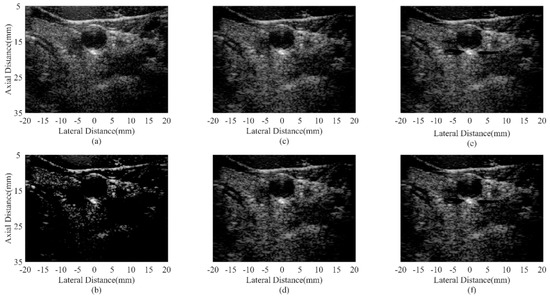

| Beamformer | CR (dB) | CNR |

|---|---|---|

| DAS | 30.61/33.98 | 1.58/1.67 |

| CF JTR-MV JTR-MV GCF JTR-ESBMV JTR-ESBMV GCF | 81.23/85.34 31.04/33.50 38.06/40.65 54.08/61.44 76.50/86.36 | 1.01/1.26 1.65/1.74 1.59/1.67 1.63/1.72 1.58/1.66 |